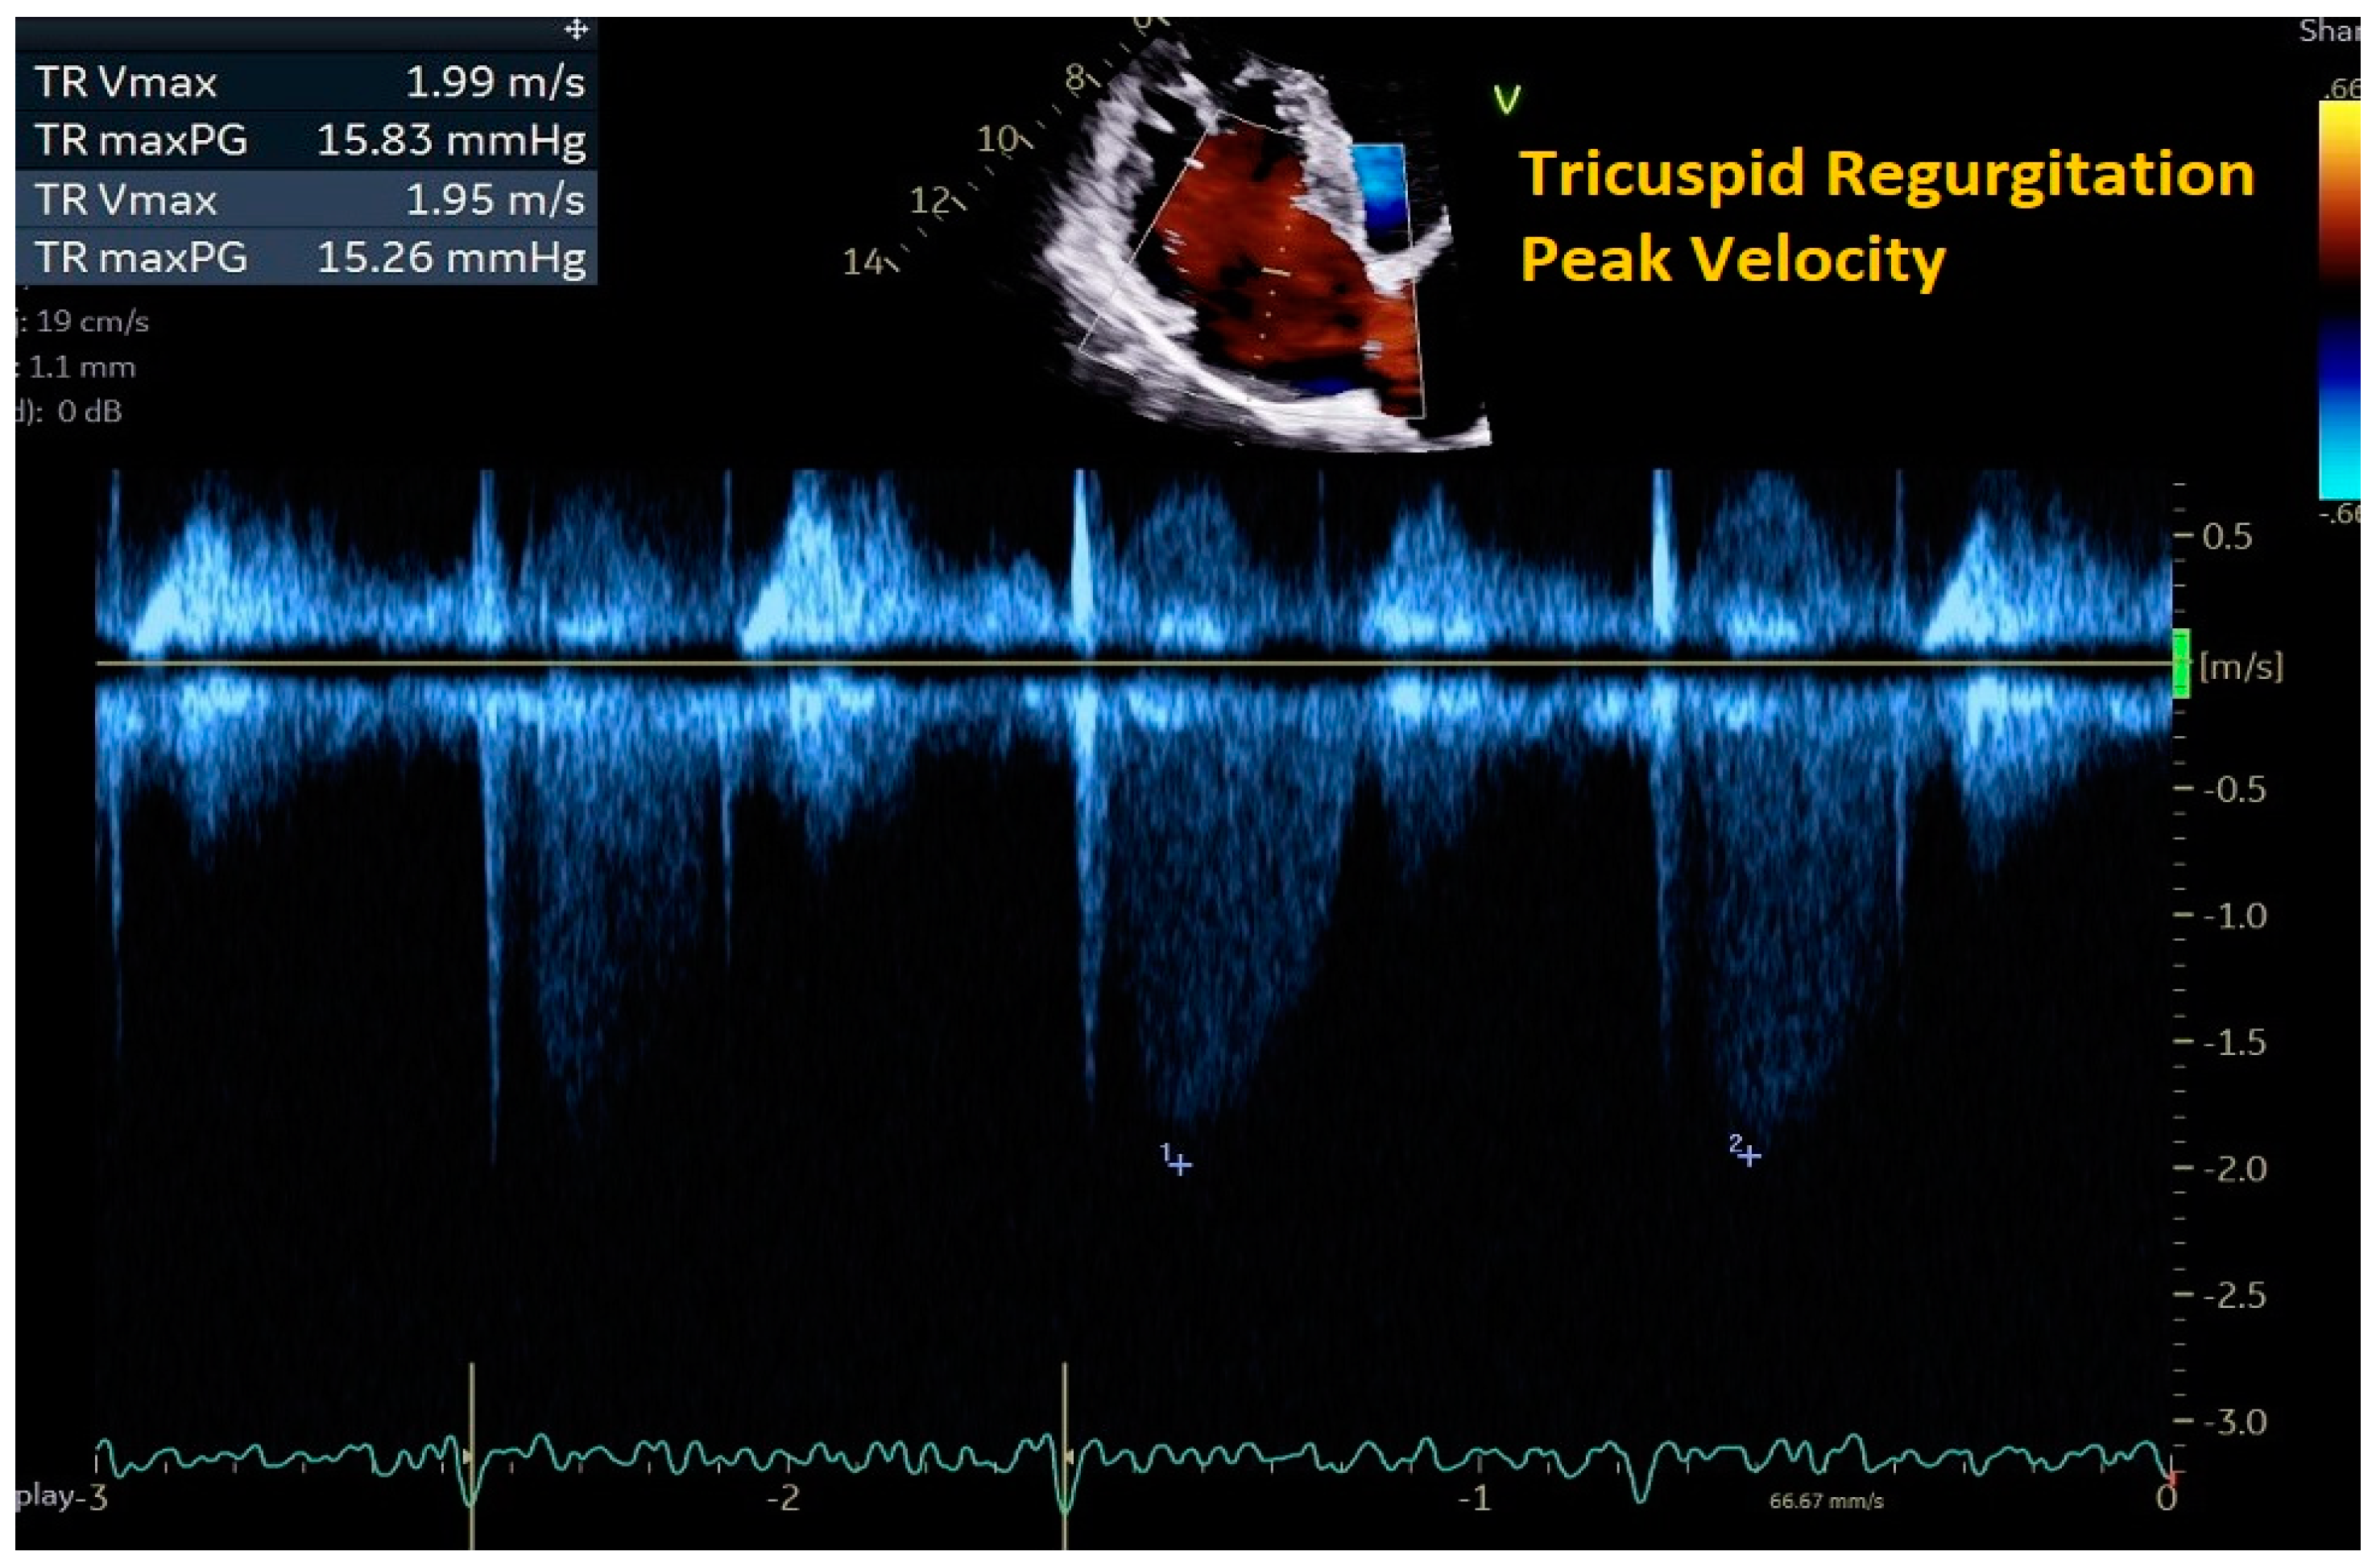

| Peak velocity of the TR jet | ≤2/8 m/s |

|

| |

| Estimated PASP using TR jet plus estimated RAP from IVC assessment | ≤35 mmHg |